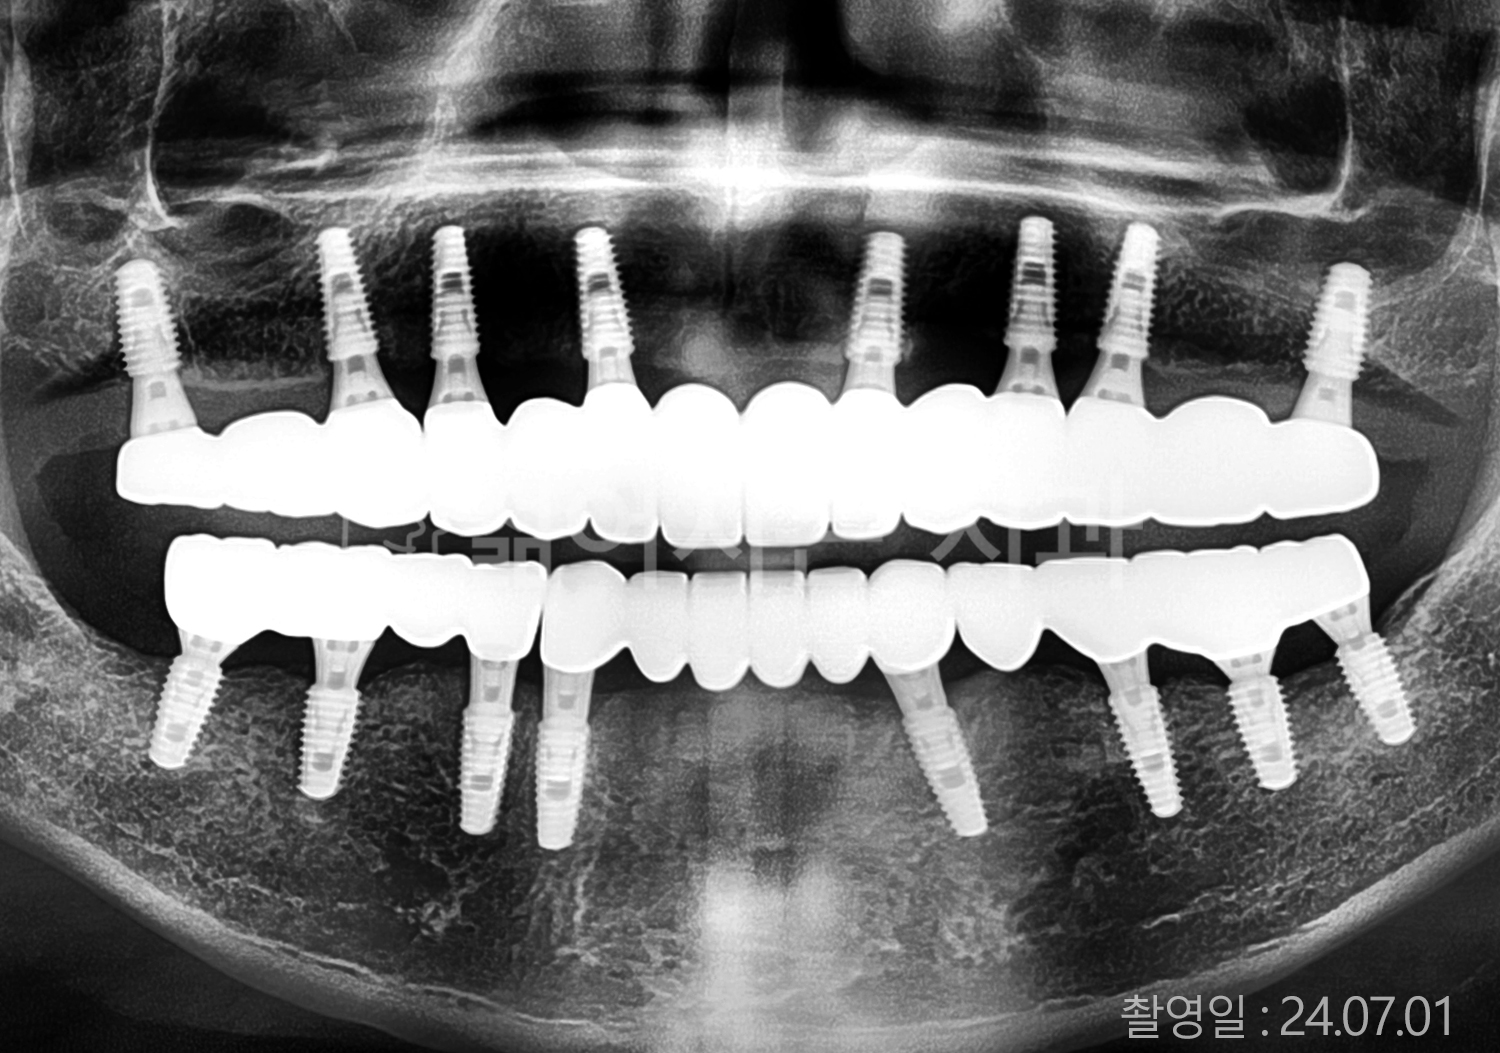

• 70대 고혈압, 당뇨 전체치아 10개 이상 임플란트

• 50대 고혈압, 당뇨 전체치아 10개 이상 임플란트

• 60대 고혈압, 당뇨 전체치아 10개 이상 임플란트

• 50대 전체치아 10개 이상 임플란트

• 70대 당뇨 전체치아 10개 이상 임플란트

• 80대 전체치아 10개 이상 임플란트

• 40대 전체치아 10개 이상 임플란트

• 60대 고협압, 고지혈증 전체치아 10개 이상 임플란트

• 60대 전체치아 10개 이상 임플란트